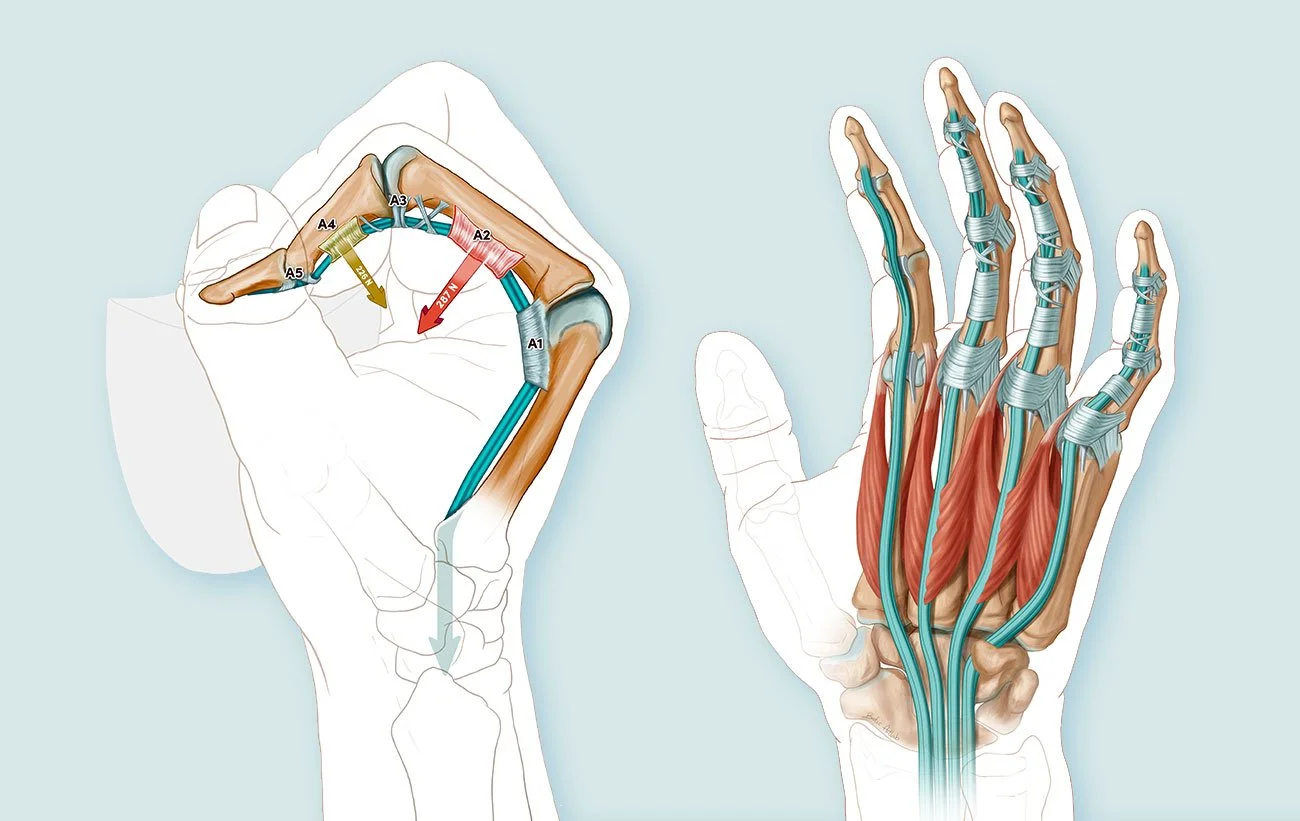

We are no strangers to the life sciences. Our medical animations animations can show how molecules interact in the body, how surgical procedures are performed, or how a new drug works at the cellular level. These visual aids help healthcare professionals, researchers, and patients understand complex medical concepts and procedures more easily.

We can help you showcase your medical device. Whether you need to present to potential investors or peers, we can create a display that will catch the attention of your audience.

We specialize in a wide variety of medical visual communications. Take a closer look:

Medical Illustration